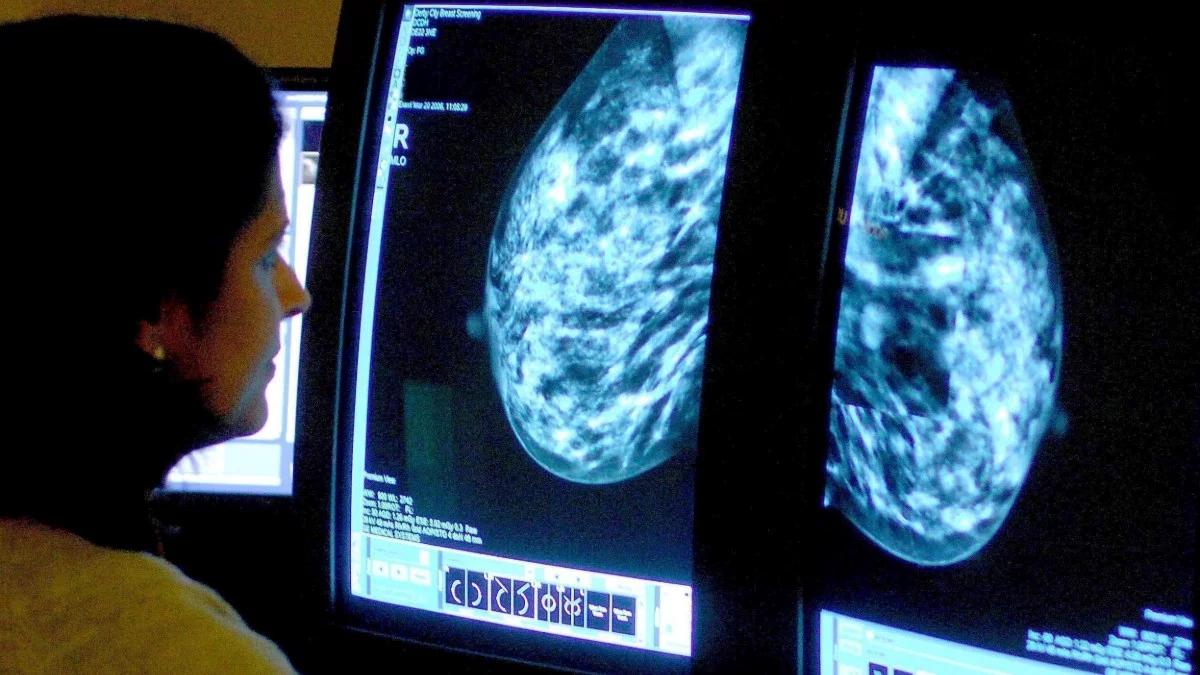

Październik to miesiąc świadomości raka piersi. Foto: PAP/PA

Październik jest miesiącem świadomości raka piersi. To najczęstszy nowotwór złośliwy u kobiet. Jednocześnie w przypadku szybkiej diagnozy w wielu przypadkach jest w pełni wyleczalny. Ekspercki przypominają o profilaktyce - nie tylko regularnym, comiesięcznym samobadaniu, ale też badaniach USG i mammografii. Tylko jedna na trzy Polki korzysta z darmowej mammografii w ramach profilaktyki raka piersi. To dwa razy mniej niż w krajach Unii Europejskiej.